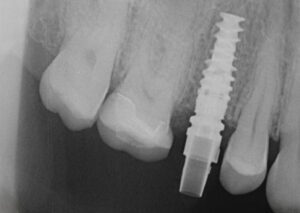

Intraoral_2022-01-24_08_43